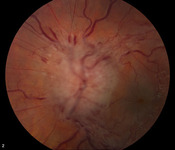

Hipertensão intracraniana idiopática

Ressonância nuclear magnética (RNM) da sela vazia em incidência sagital

Do acervo pessoal do Dr. M. Wall; usado com permissão